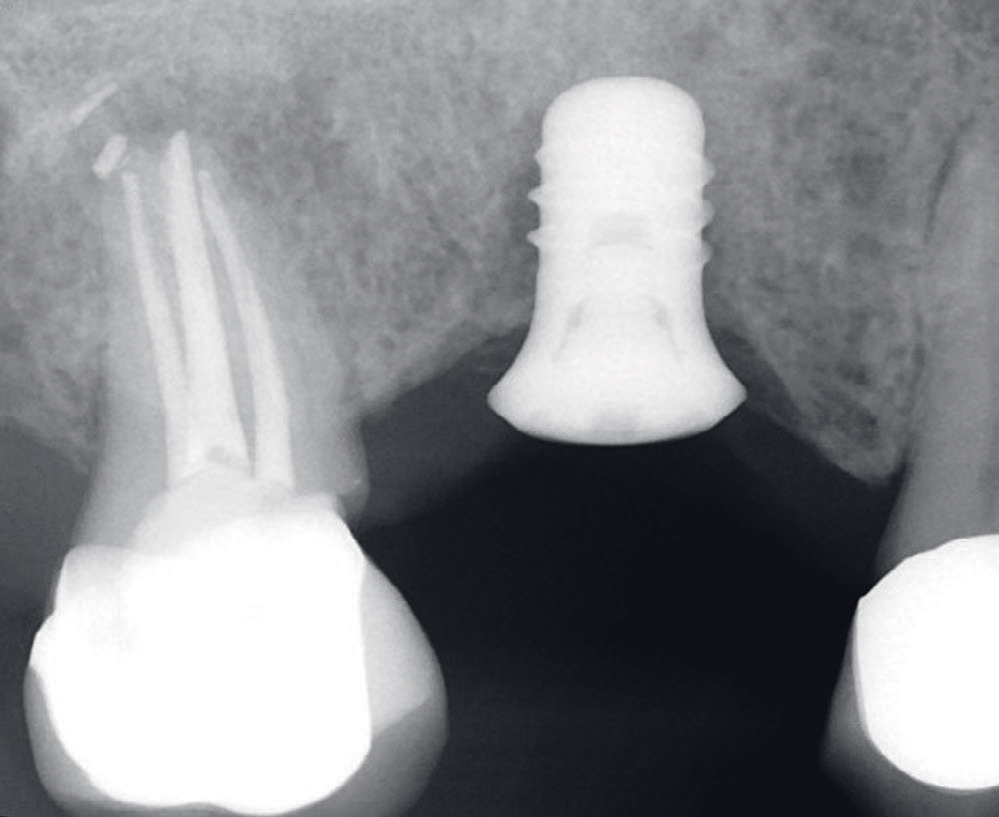

Status presens: ved ekstraoral undersøkelse av hode-/halsregion, kjeveledd og tyggemuskulatur ble det påviste stram tyggemuskulatur; ellers ingen anmerkning. Intraoral undersøkelse viste et velkonservert tannsett, god munnhygiene, men tydelig okklusal slitasje på tenner/kronerestaureringer. Pasienten informerte om tanngnissing. Mobilitet ble diagnostisert i bukko-palatinal retning på implantatkrone regio 16. Kronen hadde en voluminøs utforming og okklusalt var det tydelige slitasjeskader i porselenet særlig i det mesio-palatinale cuspområdet (figur 1). Det var ikke mulig å måle lommer eller blødning rundt implantatet. Røntgen 1. kvadrant viste tannretinerte kroner 17,15 og implantatstøttet krone regio 16. Endodontisk behandlet 17 viste apikal forandring, overskudd av rotfyllingsmateriale og sekundær karies i kronekanten mesialt, som henvisende tannlege har valgt å observere. Implantat regio 16 manglet benkontakt langs hele implantatets lengde (figur 2 og 3).

Figur 2. Røntgenbilde fra april 2018 før fjerning av kronen viser endret benmorfologi langs hele implantatets lengde.

Figur 3. Røntgenbilde fra april 2018 etter fjerning av kronen dokumenterer også endret benmorfologi langs implantatet.